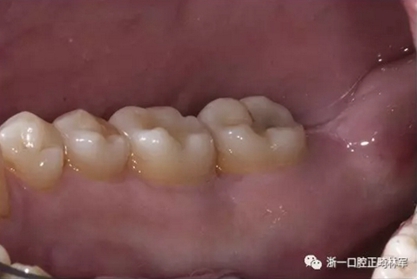

外科手術(shù)兩周后,病變愈合,患者自述無不適(圖5)。

圖5. 手術(shù)2周后病損部位愈合